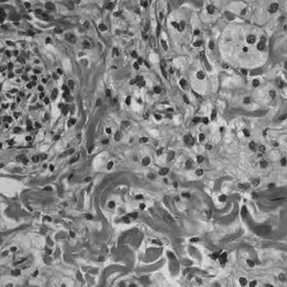

Для постановки диагноза ЭЧБ требуется проведение гистологических исследований. К типичным гистологическим признакам ЭЧБ относятся локализованные вдоль участков фиброза полиморфные ксантогранулемы, состоящие из CD68+, CD1a-, S100- пенистых гистиоцитов. При лангергансоклеточном гистиоцитозе, представлены гистиоциты классов CD68+, CD1a+.